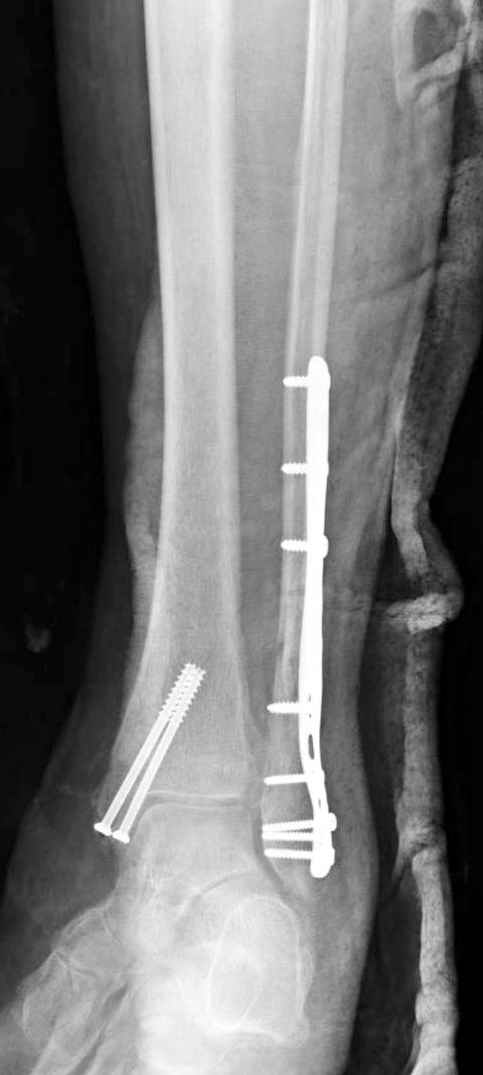

На 4-й неделе убрал спицы, с 7-й недели начал ЛФК, дозированную нагрузку, физиопроцедуры, массаж. Назначил хондропротекторы. Получилось вот что.

Rg-05.JPG

Удалены спицы, а гипса не было? 3-х лодыжечный перелом фиксировать 4 недели недостаточно. Что и подтверждается на последнем снимке - есть тенденция к подвывиху кнаружи, кзади... Что будет дальше, когда пациент начнет давать полную нагрузку?

Малоберцовая выглядит коротковатой. Профиль как-то мутный. Вообще, неплохо было бы сделать снимки в сравнении со здоровой.

Конечно, малоберцовая укорочена, надо сделать косой - мортиз снимок, тогда будеть понятно, на сколько.

Здесь финальный снимок 73 летней с

сопутствующей шизофренией, латерально бридж

пластину (соединили дистальный конец с диафизом не трогая место перелома) и медиально перкутанно

двумя шурупами. В этам случае без гипса не

обойтись.